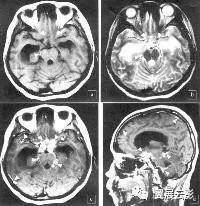

颅咽管瘤起源于原始口腔形成过程中的拉氏袋残余组织成分,是仅次于垂体腺瘤的常见鞍区肿瘤,本病占颅内肿瘤的4.7%—6.5%,男性略多于女性,以青少年多见,但成人亦可发病,肿瘤易囊变,囊内含有大量胆固醇和油性物质,此外,瘤体内还含有大量湿性角质蛋白,纤维组织及慢性炎性反应成分,约70%的肿瘤可发生钙化,本病常见的临床表现为颅内压增高症状,视力和视野损害,垂体低功,下丘脑症状,精神症状及某些脑神经受损症状。

MU扫描肿瘤可表现为短T1长T2信号,长T1长T2信号,长T1短T2信号及等T1长T2信号,总之,颅咽管瘤的MRI信号呈现多种表现形式,这与肿瘤内含有多种病理组织成分有关,80%的颅咽管瘤位于鞍上,少数位于鞍内,病变可侵入第三脑室内,极少数可侵入蝶鞍内或颅低,肿瘤呈圆形,类圆形或不规则形。增强扫描肿瘤实体部分及囊壁明显强化,囊变部分不强化。